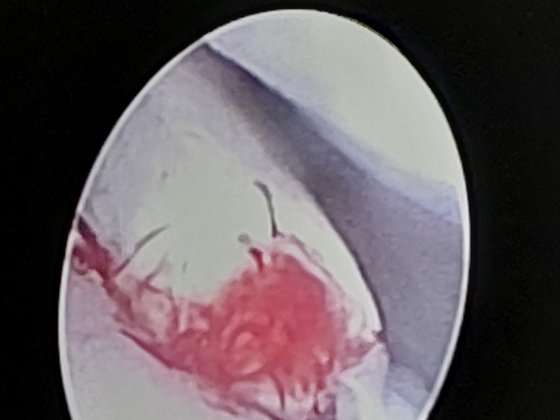

Artroskopie

Její výhodou oproti standardním kloubním zákrokům je minimální invazivita a tím i zátěž zvířete. Tato metoda navíc umožňuje prohlédnout i odlehlé části kloubů, kam je jinak velmi obtížný přístup. Malé ranky určené k přístupu do kloubů výrazně snižují riziko pooperačních obtíží, malé poškození tkáně urychluje rekonvalescenci zvířete a jeho návrat do normálního života.

Rozšíření artroskopických metod ve veterinární medicíně určitě představuje jeden z nejdůležitějších milníků ve veterinární ortopedii.